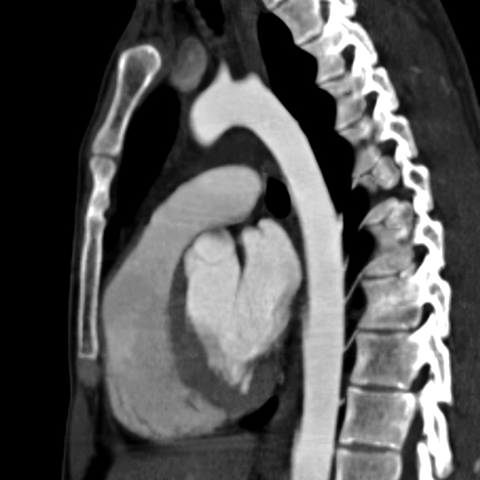

Normal Heart (CT) [4 of 6]